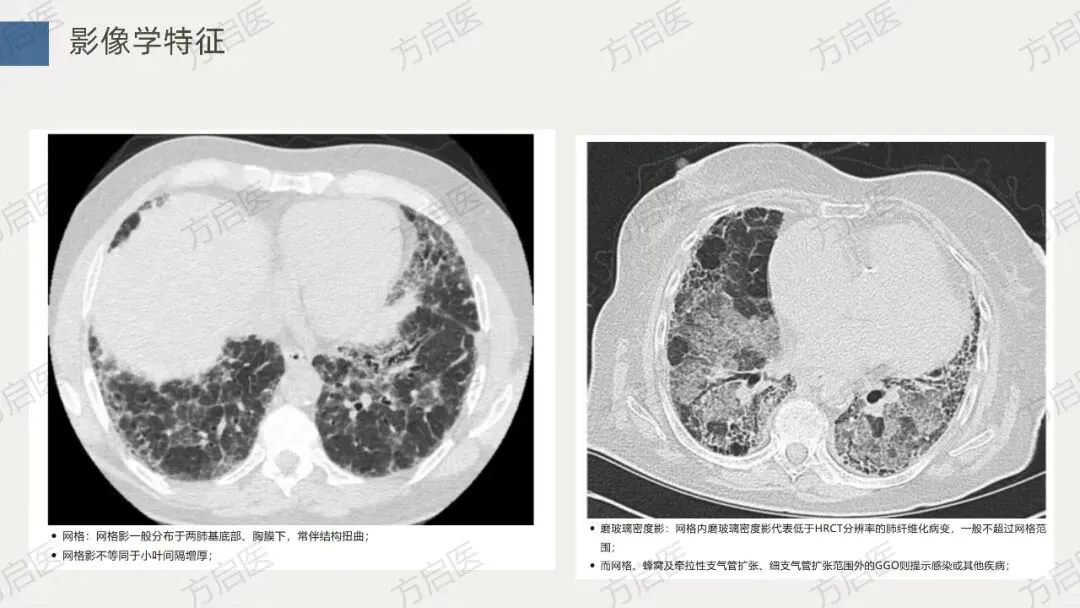

特发性肺纤维化是一种进行性疾病,这意味着它会随着时间推移逐渐恶化。肺部的瘢痕组织无法被身体或任何药物修复,目前也没有任何治疗方法可以阻止或逆转瘢痕的形成。